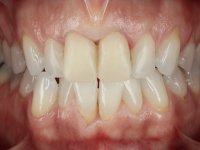

Paciente do sexo feminino com 41 anos de idade, não fumadora. Apresentava duas coroas sobre espigões falsos cotos fundidos nos dentes 1.1 e 2.1. As coroas apresentavam-se com infiltrações cervicais com exposição da superfície radicular. A papila gengival mediana, apresentava-se ligeiramente retraída. O espaço mesio-distal correspondente às duas coroas mostrava-se alto e estreito. Apresentava um ligeiro apinhamento dos incisivos inferiores, bem como uma pequena retração gengival. No sorriso era bem visível a zona cervical das coroas, mostrando um aspeto acinzentado correspondendo ao escurecimento radicular. No exame imagiológico verificou-se que o tratamento endodôntico não estava tecnicamente satisfatório, mas assintomático à quase 10 anos.